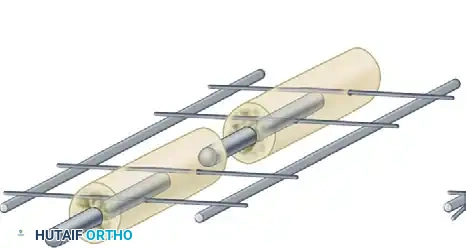

Biomechanics of External Fixation

Understanding the biomechanics of external fixation is critical for the orthopedic surgeon. The stability of the frame dictates the mechanical environment at the fracture site, which in turn influences the type of bone healing (primary vs. secondary).

Factors Influencing Frame Stiffness

The rigidity of an external fixator construct is determined by several modifiable variables:

* Pin Diameter: The stiffness of a half-pin is proportional to the fourth power of its radius ($r^4$). Increasing the pin diameter is the single most effective way to increase frame rigidity. However, pin diameter should not exceed one-third of the bone's diameter to prevent stress risers and subsequent iatrogenic fractures.

* Distance from Bone to Rod: The closer the longitudinal rod is to the bone, the stiffer the construct. The rod should be placed approximately 2 to 3 cm from the skin to allow for postoperative swelling while maximizing stability.

* Pin Spread: Increasing the distance between the two outermost pins in a single bone segment increases the stability of the construct.

* Number of Pins: Increasing the number of pins per segment increases stiffness, though the biomechanical advantage diminishes after three or four pins per segment.

* Number of Bars: Adding a second longitudinal bar (creating a stacked or double-bar construct) significantly increases stiffness, particularly in bending and torsion.

* Multiplanar Constructs: Placing pins in different planes (e.g., a delta frame or biplanar construct) dramatically increases torsional and bending rigidity compared to a uniplanar frame.